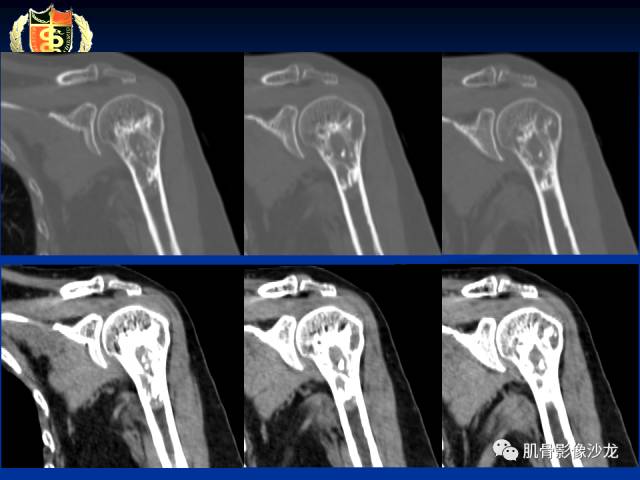

骨淋巴瘤及软骨肉瘤两例CT及MR影像表现

内生软骨瘤?

有症状,有骨膜反应,还是考虑肉瘤比较合适

目前看考虑软骨来源是合理的

这些应该是钙化吧

还是支持软骨肉瘤

里面的高信号是软骨吧